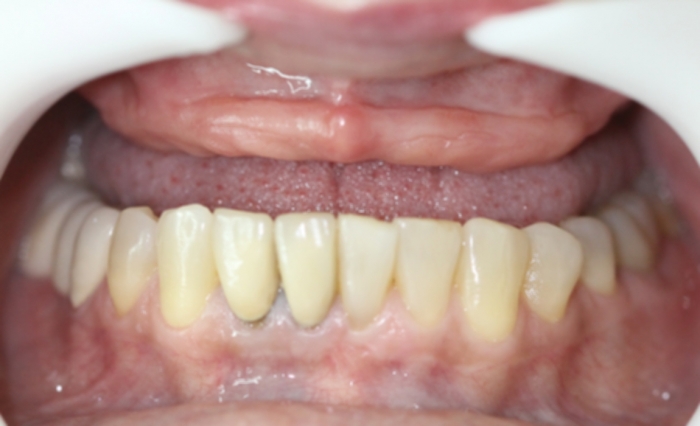

Prótese Provisória

Sorriso Final com a prótese provisória